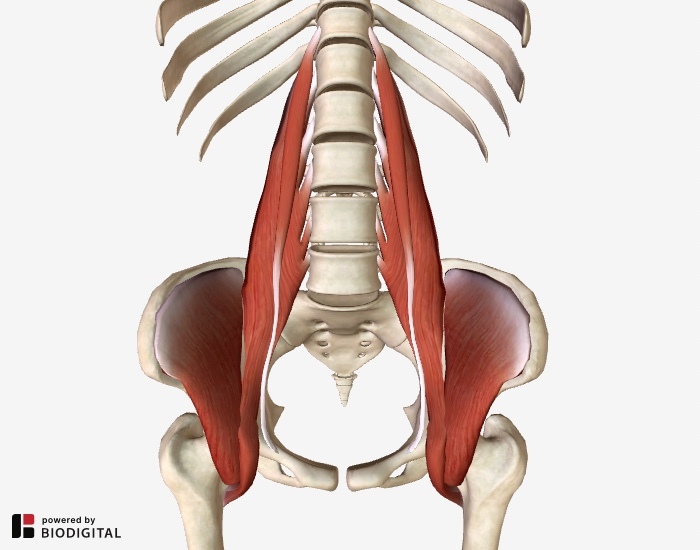

which is this muscle?

what is it innervated by?

movement?

iliopsoas!

femoral nerve

movement: hip flexion - major muscle of hip flexion !!